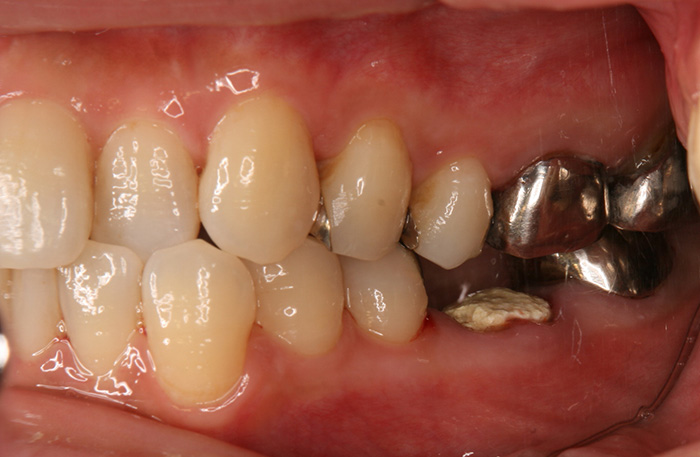

歯の移植の症例

Before

After

親知らずの歯を移植したケースです。患者様はとても喜ばれておりました。